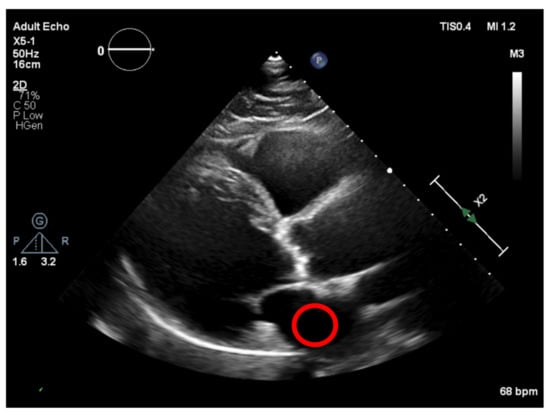

Achieving a dynamic threshold will normalize our echocardiography images, allowing our model to identify the calcium in different cases with different gains. The calcium presence can be seen in Figure 18 and is marked by a red circle.

Figure 18. Calcium in the binarized image.